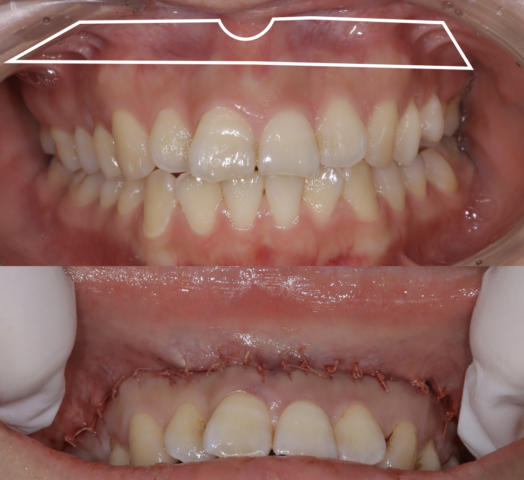

笑っても唇を上げにくくするリップリポジショニングで治療

白枠の粘膜を切り取って縫い付けることで笑っても唇を上りにくいようにします。

リップリポジショニングは歯冠長延長術より改善量が多いですが10%くらいの割合で起こす後戻りが問題でした。